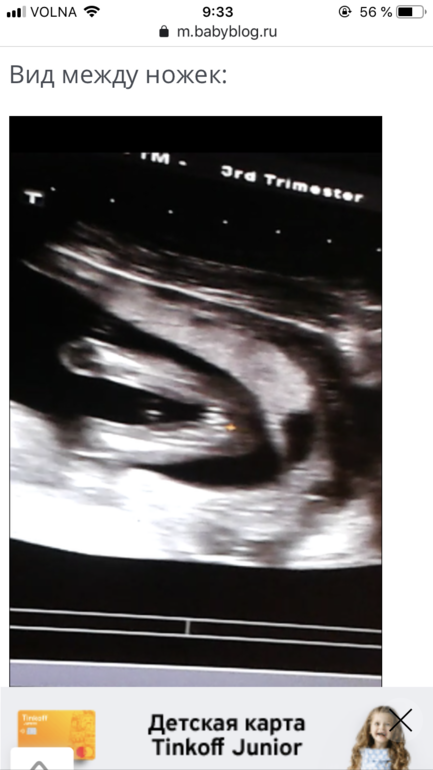

А точно ли девочка?

Врач сказал сидит на попке, неудобно со всех ракурсов посмотреть, но девочка.

Может у кого были такие же фото?

А то муж мечтает о девочке, радовать или рано?

Врач сказал сидит на попке, неудобно со всех ракурсов посмотреть, но девочка.

Может у кого были такие же фото?

А то муж мечтает о девочке, радовать или рано?

Я как поняла первое фото со спины и всё думаю, может это яйки и спереди стручочек торчит 🤭

Я не врач, конечно, но тут, по-моему, точно девочка)